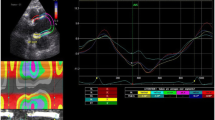

As in a prior publication of ours [12], calculations of regional and global thoracic ascending aortic mechanics relied on 2D-ST technology. With a line manually drawn along the inner aspect of aortic wall in short axis, additional lines were automatically generated (via 2D-ST) at the outer aspect of vessel wall. Considering the relative thinness of vascular walls (compared with cardiac walls), region of interest width was reduced to the minimal value allowable by software, as previously suggested [21]. The initial systolic frame generally served as the frame of interest, to include maximal aortic wall expansion and recoil. As in other instances [10, 22], aortic wall was divided into six equidistant regions, all similar in size. In each region, numeric expressions of each 2D-ST variable represented mean values calculated from all points in arterial segments. These were color-coded and shown as a function of time throughout the cardiac cycle. Quantitative curves, depicting all regions, were possible for each 2D-ST variable. The tracking process and conversion to Lagrangian strains were performed offline, using dedicated software. CAASR curves generated here were aligned with those generated elsewhere [6, 9] and included a positive early systolic peak. Global CAASR was then calculated as the mean of peak values for the six segments (Fig. 1).

Global CAASR (s−1) generated from short axis view of aorta, 2–3 cm above aortic valve. (a) Thoracic ascending aorta region of interest (short axis view). (b) Color M-mode of CAASR for all regions during cardiac cycle. (c) Color-coded curves of defined aortic segment (depicted in figure); global CAASR indicated by white dotted curve. Circumferential SR (first peak after ventricular systole) assumes early positive value due to vessel wall expansion